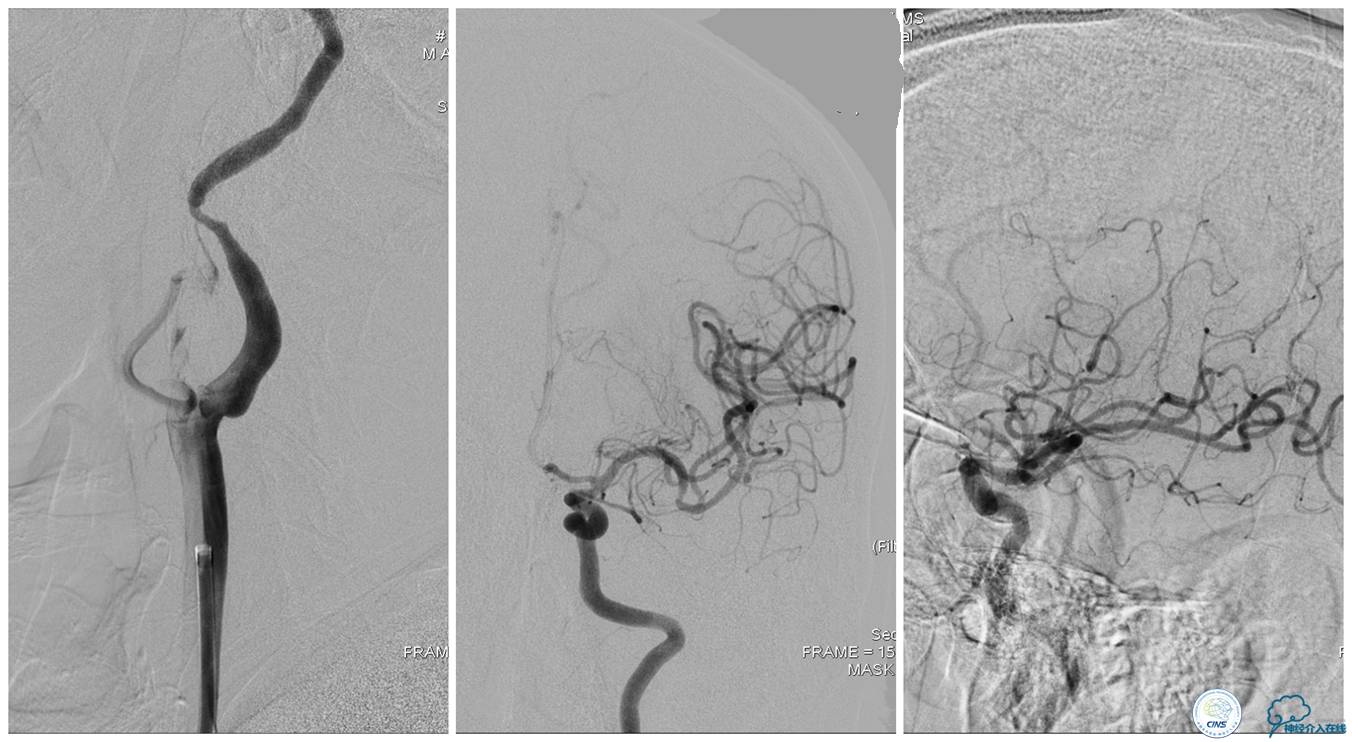

▼21:27穿刺成功,TOT 297min。左侧颈总动脉末端、颈内动脉起始部及颈外动脉起始部长条状血栓形成,随血流晃动,同侧大脑中动脉、大脑前动脉显影良好。

▼选用NAV 6 7.2 mm远端保护装置置于左侧颈内动脉C1段末端,将8F Gulding先后置于颈总动脉及颈内动脉开口部,50 ml注射器反复抽吸,抽出大量血栓。

▼颈总动脉及颈内动脉血栓抽吸完全,远端血流较前好转,TICI 3级。

▼血栓: